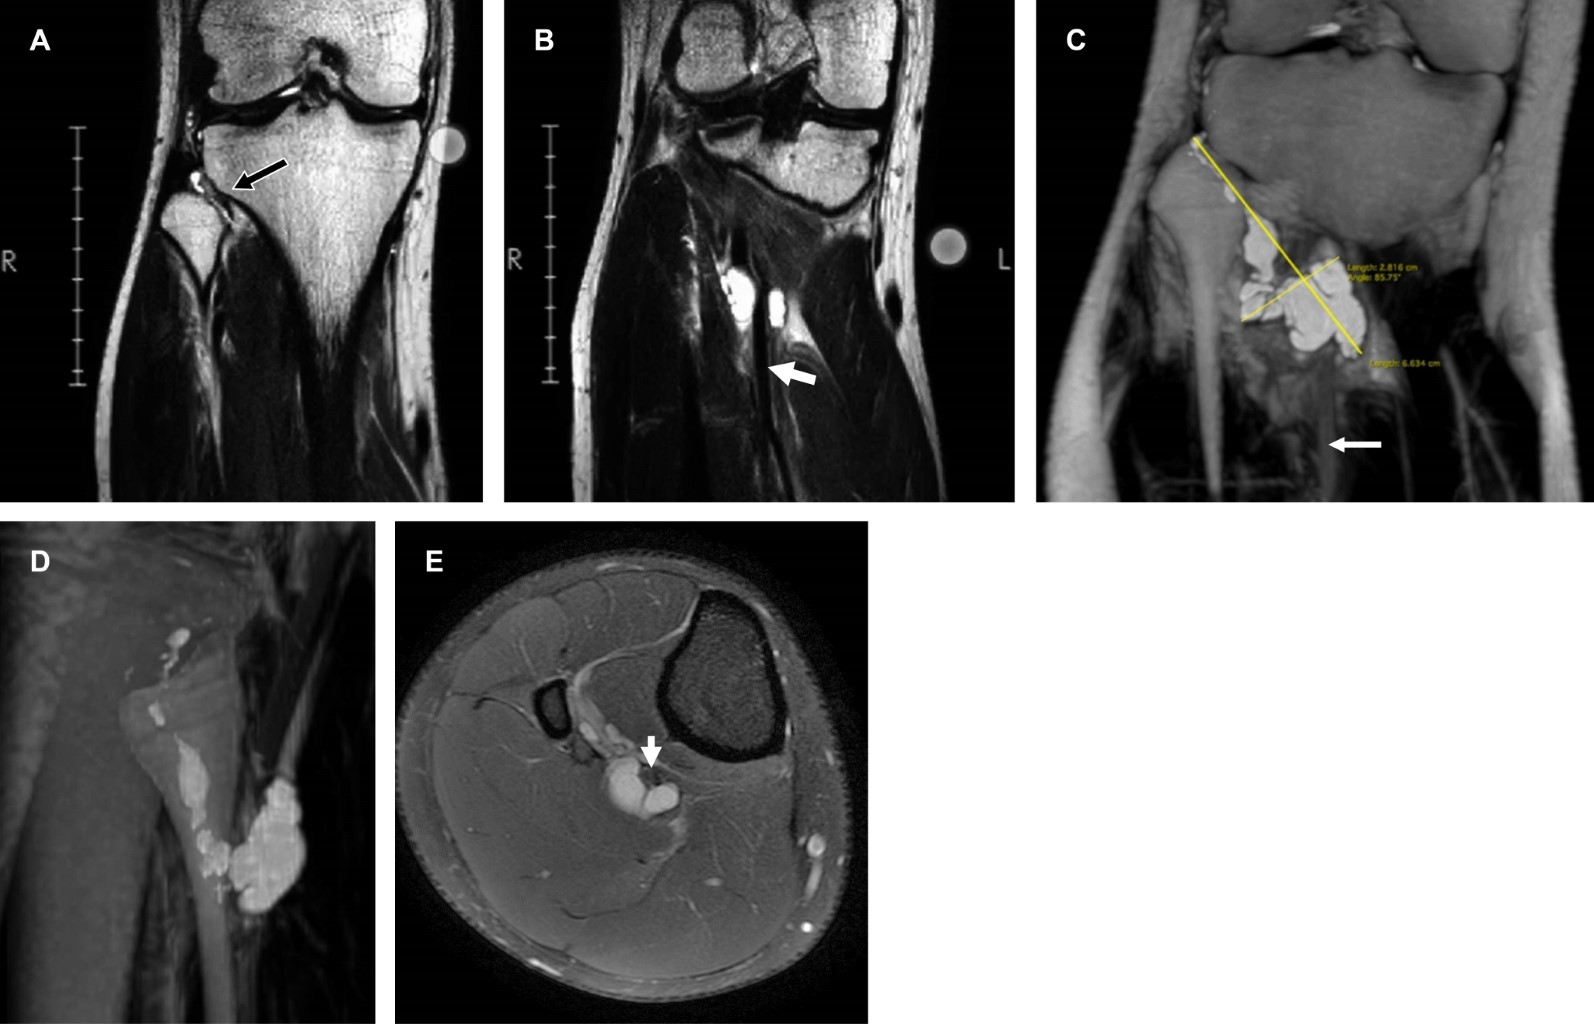

A la exploración dirigida: arcos de movilidad completos en miembro pélvico derecho; el examen clínico muscular en escala de Daniels mostró glúteos mayor, medio y menor, semimembranoso, semitendinoso, bíceps crural, tibial anterior, peroneos y extensor común de los dedos en 5/5; tríceps sural, plantar delgado, tibial posterior y flexores de los dedos en 3/5; hipoestesia en territorio plantar del talón y nervio plantar externo, abarcando mitad externa de cuarto dedo del pie. Reflejo rotuliano normal, Aquíleo disminuido. Con diagnóstico de compresión del nervio tibial a nivel de vértice inferior de hueco poplíteo, se efectuó resonancia magnética que mostró ganglión dependiente de articulación tibioperonea proximal. Se derivó a cirugía articular para su manejo quirúrgico.

La resonancia magnética es de elección5 para su estudio, determinando su localización anatómica y extensión hacia planos profundos (Figura 1). El tratamiento quirúrgico se utiliza cuando el ganglión es sintomático,1 ya que existe alta tasa de recidiva con manejo conservador como punción, aspiración o inyección de esteroides, lidocaína u otras sustancias.

Figura 1